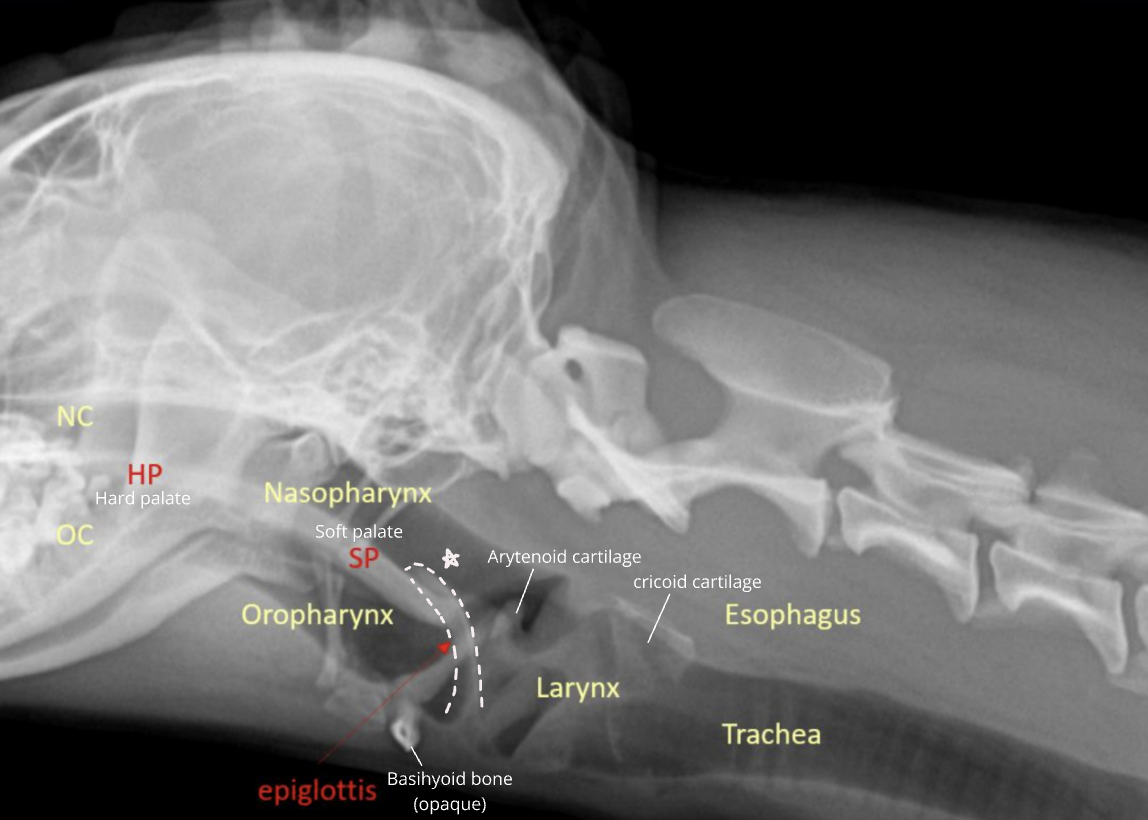

| Upper respiratory system |

![]() |